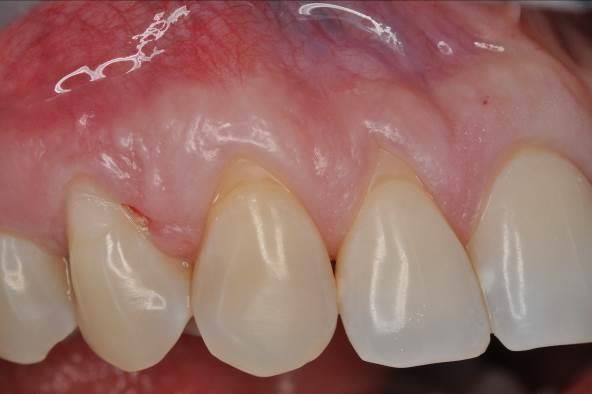

01/06 - Pre-surgical situation. Multiple adjacent gingival recessions at teeth 12, 13 and 14.Multiple gingival recessions treated with the modified coronally advanced flap in conjunction with mucoderm® and Straumann® Emdogain® - Dr. D. B. Hangyási

Pre-surgical situation. Multiple adjacent gingival recessions at teeth 12, 13 and 14.